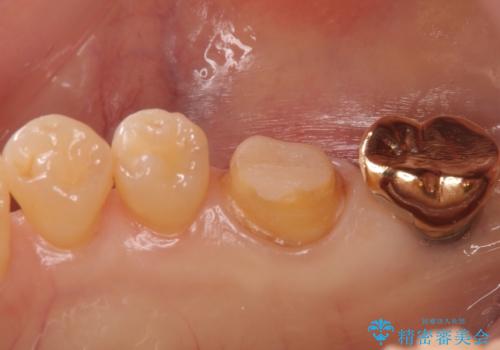

- 右下6 仮歯+セラミッククラウン 11,000円+121,000円費用は治療当時の料金となります

クラウンでは歯のがたつきを修正することもできます。

虫歯の除去と歯の捻転の両方を解決することができました。